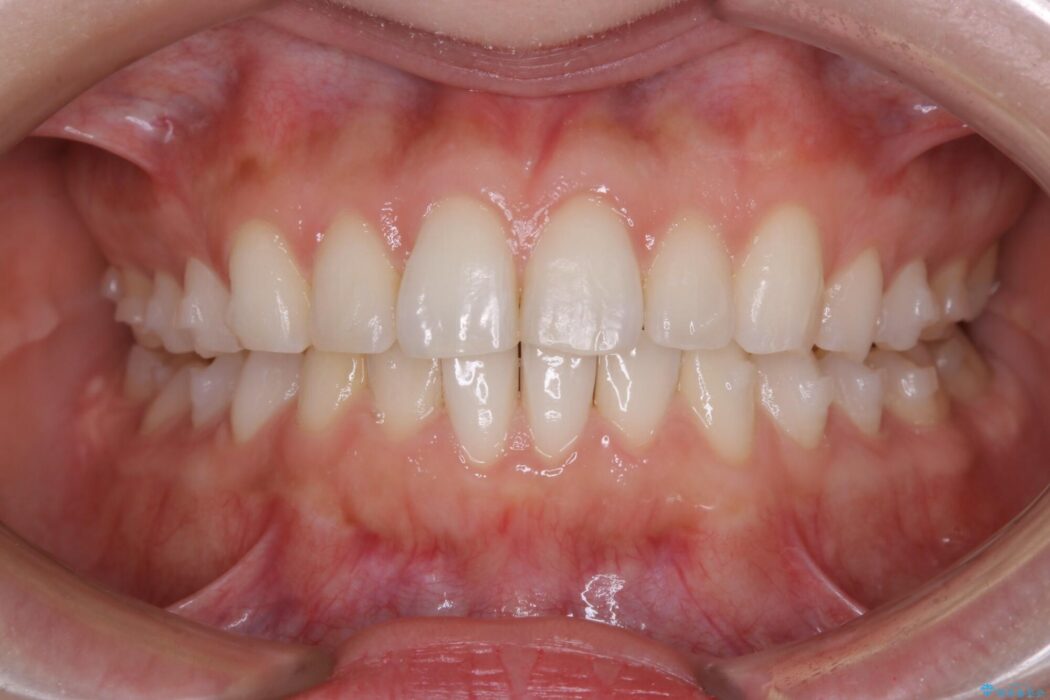

半年という短期間でスピード治療が完了しました。

治療期間、治療後の出来ともに大変ご満足いただけました。

患者様の歯の状態によってはマウスピース治療でも部分矯正のように短い治療期間で歯列の矯正をすることが可能です。

治療期間・費用が共に抑えられるため、今まで矯正への一歩を踏み出せずにいた方でも満足のいく治療が受けられる場合があります。